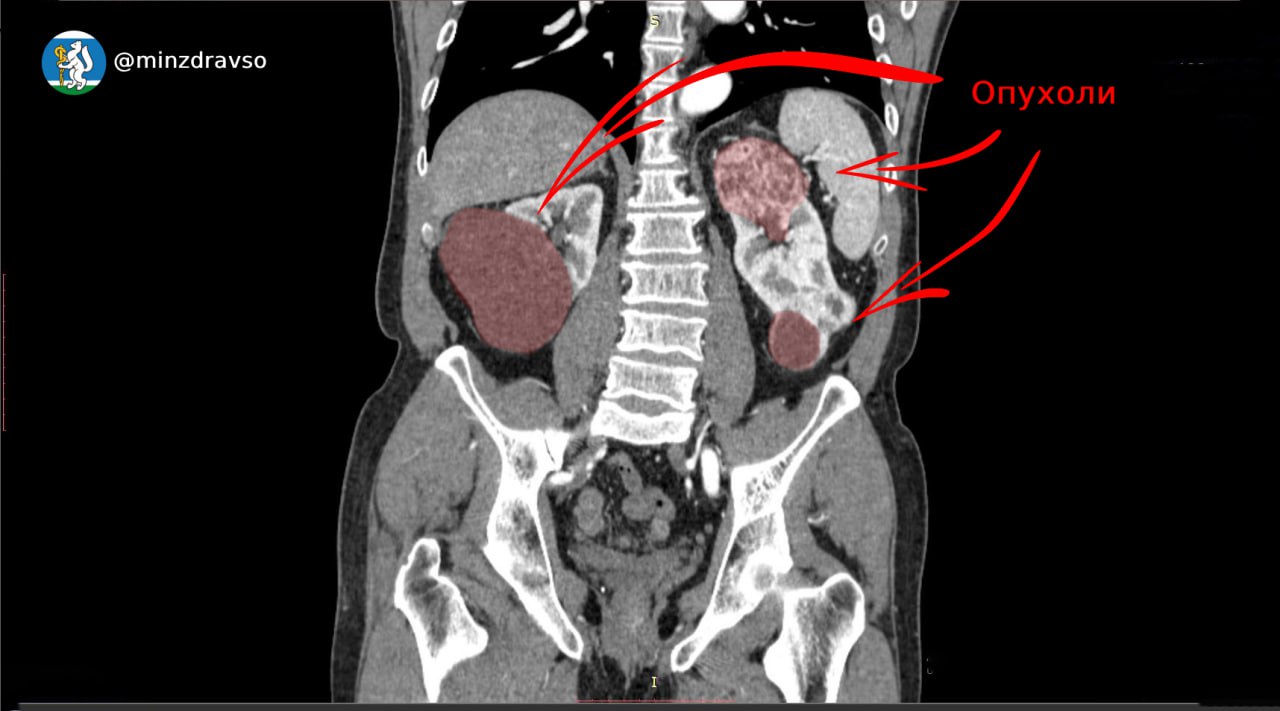

В Екатеринбурге спасли мужчину с синхронным раком почек